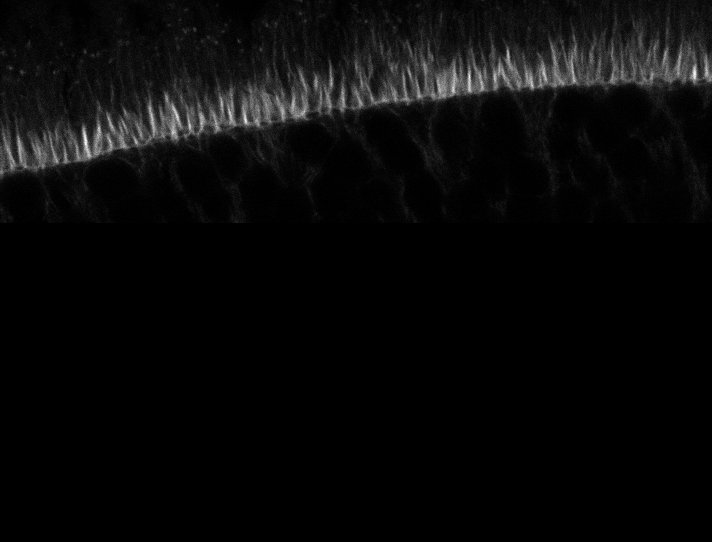

Healthy Retina

Unhealthy Retina